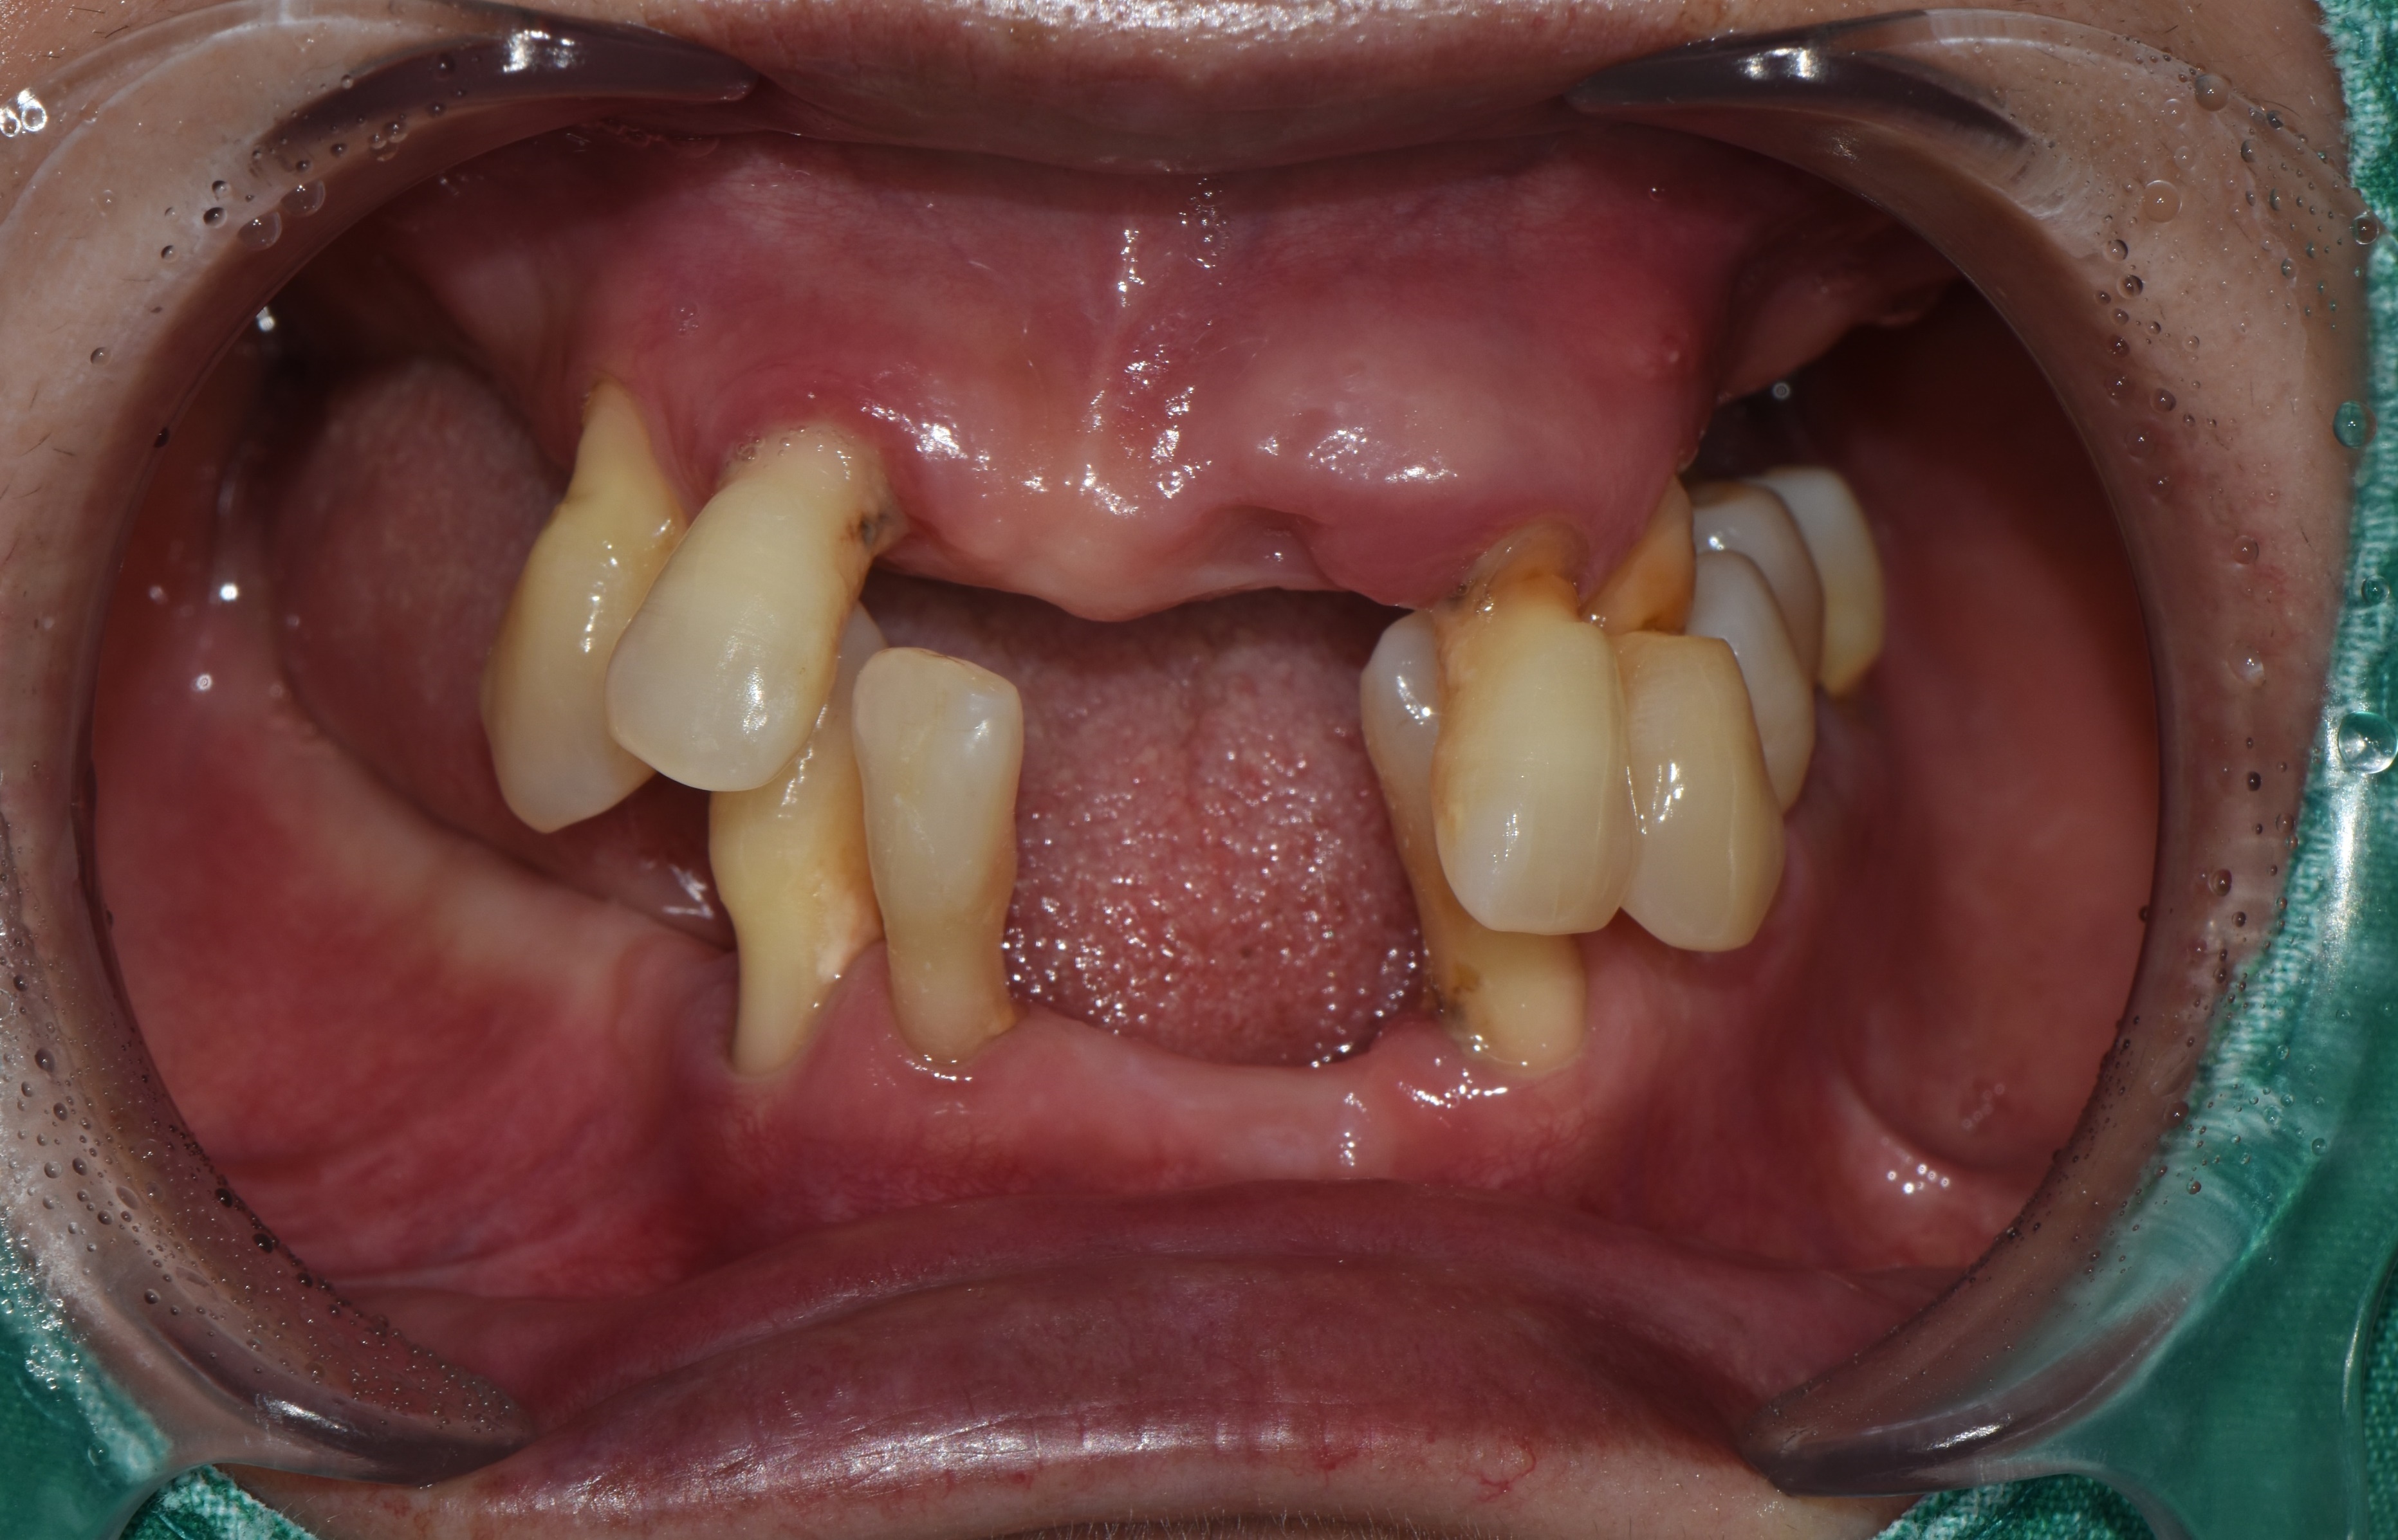

심한 잇몸병으로 전체임플란트 치료를 진행한 환자분의 치료 증례 2026-02-20 hit.240 |

촬영일시: 2025.06.05